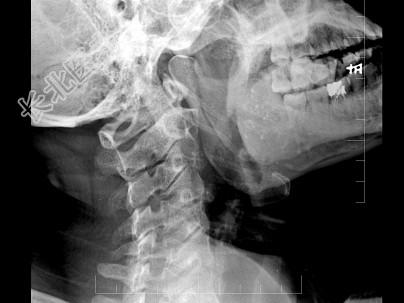

- 多项选择题女,37岁, 咽部异物感、咽痛伴反射性耳痛、头颈部不适近1年余,如图所示, 下列描述正确的是 ( )

A、左侧茎突长约3.5cm

B、右侧茎突长约4.0cm

C、双侧茎突过长综合征

D、右侧茎突过长综合征

E、正常茎突